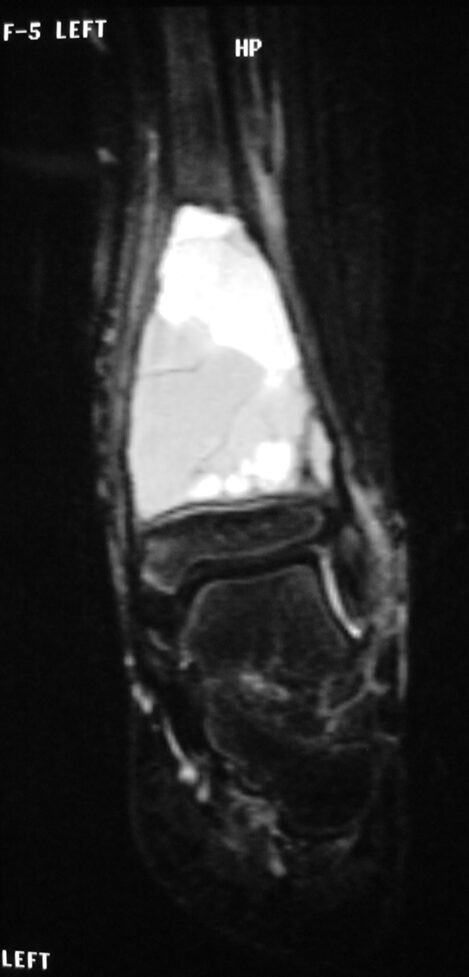

MRI

- Geographic well circumscribed

- High signal on T2 weighted MRI images

- Fluid/Fluid level (T2) are highly characteristic

Fig 2 a-e. MRI of an ABC of Distal Tibia: Fig 2 a-c: geographic cystic expansile lesion with fluid-fluid levels. The fluid-fluid levels are caused by bleeding into the cavities. The blood collects and the degredation products settle to the gravity dependent areas of the cavities. This shows up as fluid-fluid levels on the MRI. Fig 2 d,e: This is a gadolinium enhanced MRI of the ABC of the distal tibia. There is peripheral and septal enhancement indication cyst formation. The contrast outlines the cystic cavities but does not enter into the center